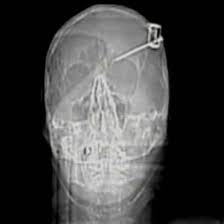

NEW "MICROTECH"

NEW "MICROTECH"